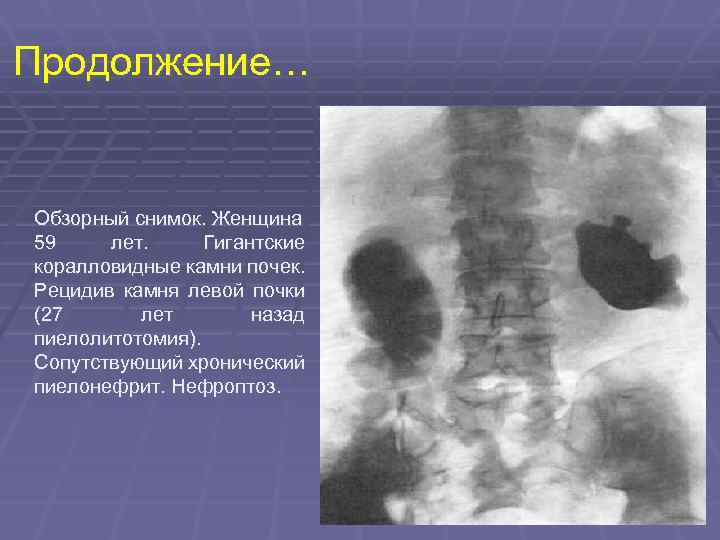

Экскреторная урография при нефроптозе: диагностические изображения